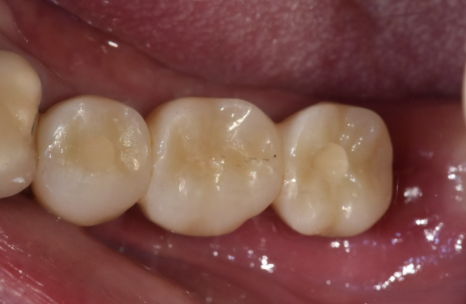

3개월의 기다림 끝에,

양쪽 어금니 모두

250905

흔들리고 냄새나던 브릿지 대신,

단단하게 고정된 임플란트가 생기니

무엇보다 '씹는 맛'이 다르다고 하십니다.

250403 (전) 250905 (후)